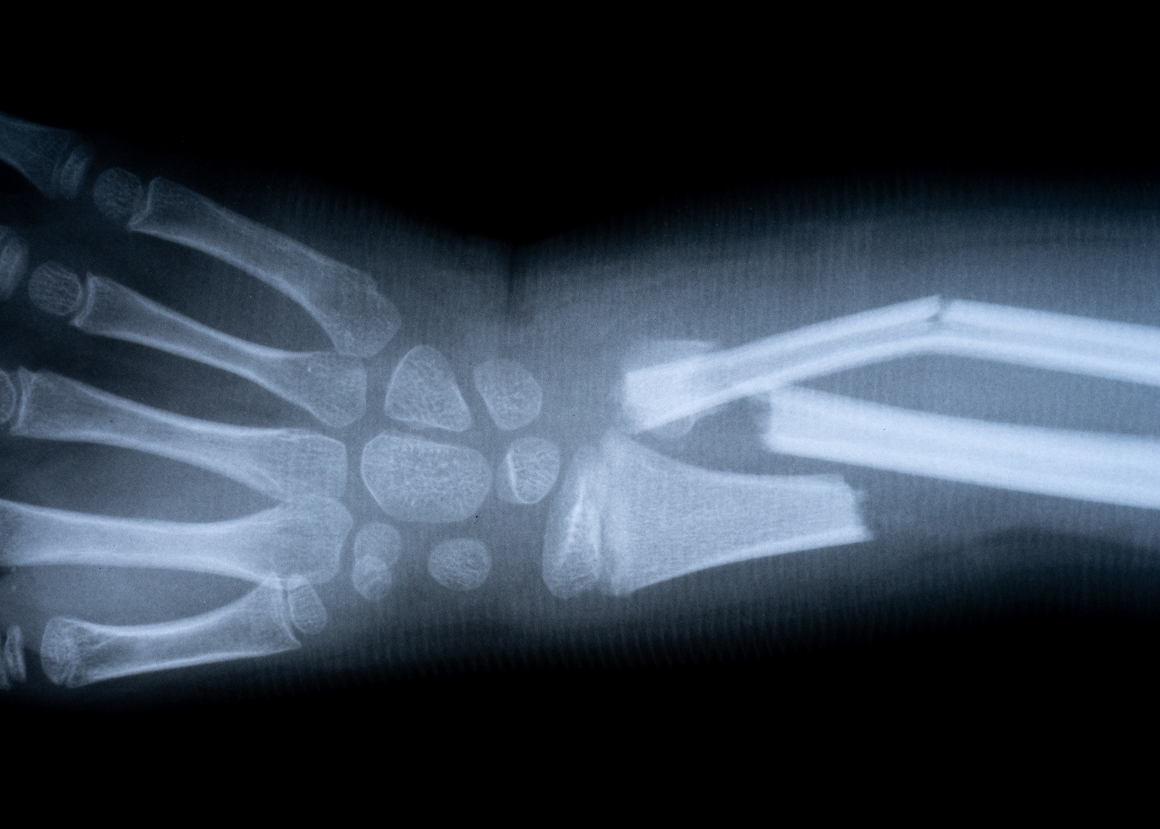

Но главный метод — рентген. Он выявляет характер повреждения: линию излома и наличие смещения. Снимок делают минимум в двух проекциях.

ВИДЫ ПЕРЕЛОМОВ РУКИ

Один из главных критериев — открытость. Выделяют разные виды переломов по этому признаку: открытые и закрытые. При открытых повреждениях кость пронзает кожу. Видны рана и осколки.

При закрытом переломе кожа остается целой — раны нет. При этом сама кость может быть сильно сломана: со смещением, на несколько частей или с повреждением сустава. Такие переломы — самые распространённые и случаются у людей любого возраста.

Еще один параметр — линия излома. Она может быть поперечной, косой, спиралевидной или оскольчатой. Чем сложнее линия, тем дольше идёт регенерация костной ткани.